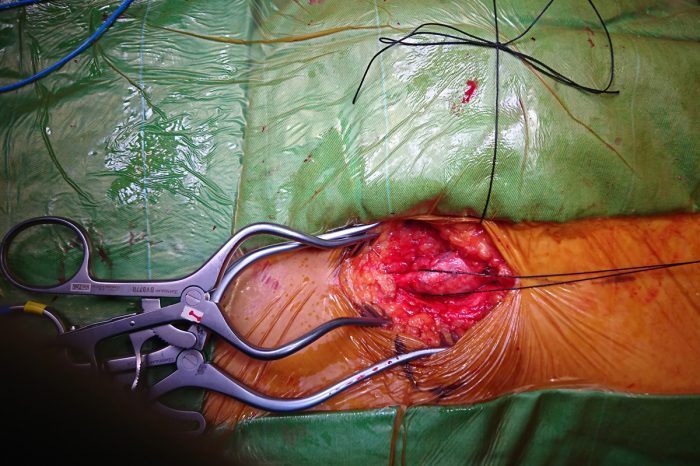

Hastanın ve hastalığın özelliklerine göre, ana yüzeysel toplardamarın çıkartılması (stripping, kapak tamiri, perforan damarların …Devamı